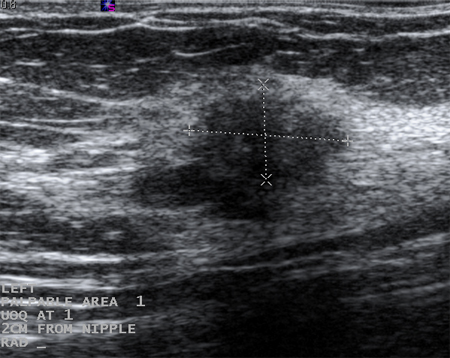

Cysts that recur or do not completely resolve with aspiration should be biopsied to rule out malignancy. Similarly, biopsy should be considered in complex cysts or those with solid elements. Sonographic characteristics may classify a solid mass as either 'probably benign' or 'suspicious'. Masses that are smooth, oval, lobulated, with clearly defined margins, and that are wider than they are tall, are often benign (e.g., fibroadenoma). If a mass is irregular, heterogeneous, has poorly defined or spiculated margins, and is taller than it is wide, it is considered 'suspicious' for malignancy, and biopsy should be undertaken.[Figure caption and citation for the preceding image starts]: Ultrasonographic image of a complex cystCourtesy of Dr Lane Roland, University of Louisville; used with permission [Citation ends].

[Figure caption and citation for the preceding image starts]: Ultrasonographic image of a fibroadenomaCourtesy of Dr Lane Roland, University of Louisville; used with permission [Citation ends].